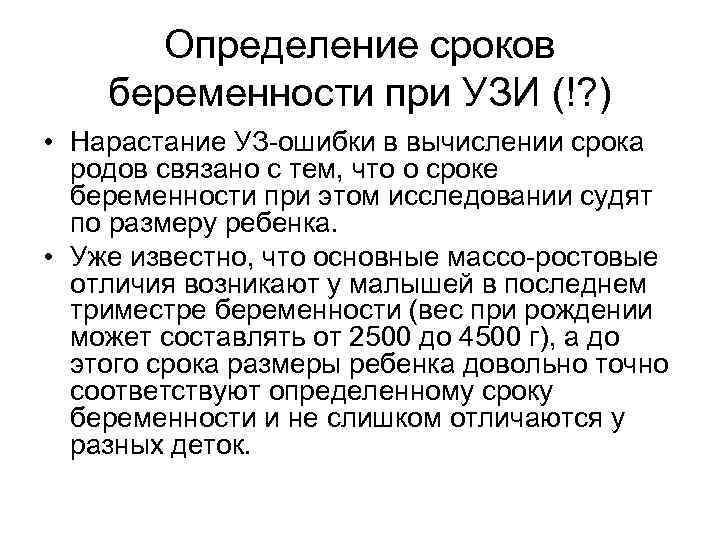

Определение сроков беременности при УЗИ (!? ) • Нарастание УЗ-ошибки в вычислении срока родов связано с тем, что о сроке беременности при этом исследовании судят по размеру ребенка. • Уже известно, что основные массо-ростовые отличия возникают у малышей в последнем триместре беременности (вес при рождении может составлять от 2500 до 4500 г), а до этого срока размеры ребенка довольно точно соответствуют определенному сроку беременности и не слишком отличаются у разных деток.

Определение сроков беременности при УЗИ (!? ) • Нарастание УЗ-ошибки в вычислении срока родов связано с тем, что о сроке беременности при этом исследовании судят по размеру ребенка. • Уже известно, что основные массо-ростовые отличия возникают у малышей в последнем триместре беременности (вес при рождении может составлять от 2500 до 4500 г), а до этого срока размеры ребенка довольно точно соответствуют определенному сроку беременности и не слишком отличаются у разных деток.